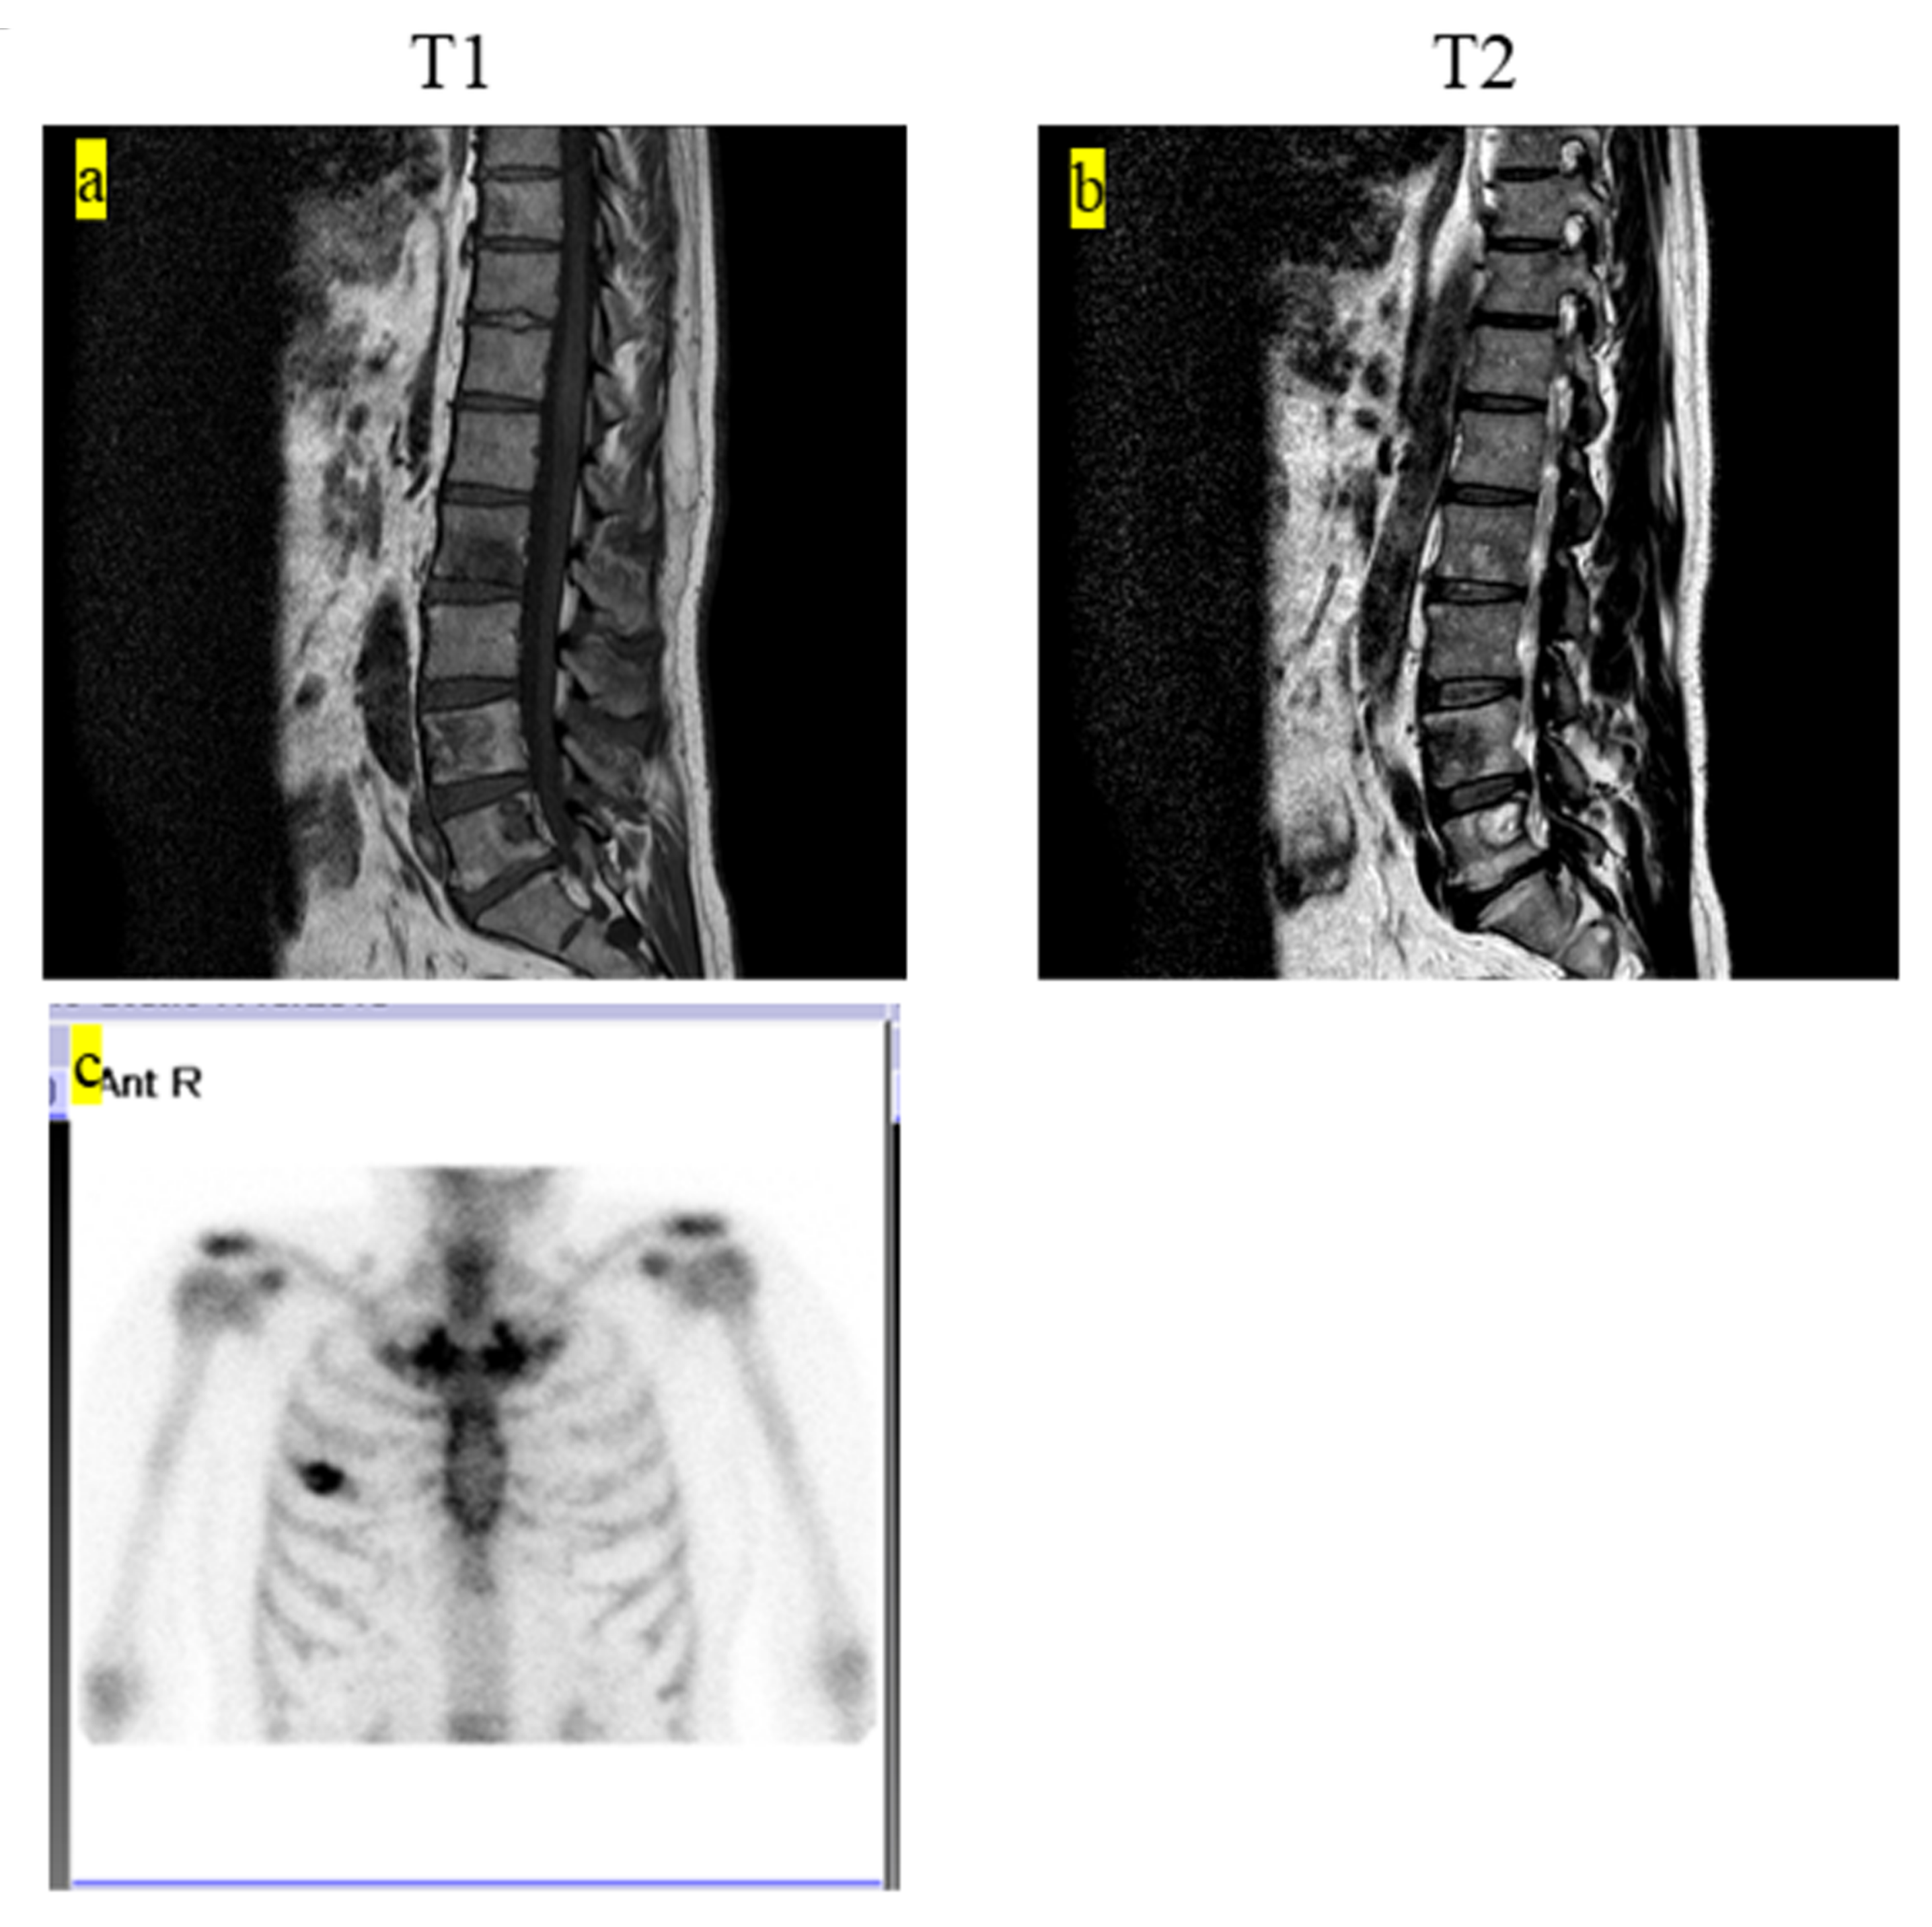

| 2 | 60 | M | Second, third, fourth, fifth lumbar, Th10, rt fourth rib, sacrum, pelvic | Radiography, MRI, PET-CT | Without symptoms | Hepatitis B | Fifth lumbar | Chemotherapy (6-mercaptopurine 110 mg, MTX 2.5 mg, PSL 5 mg) | CDF | 63 |